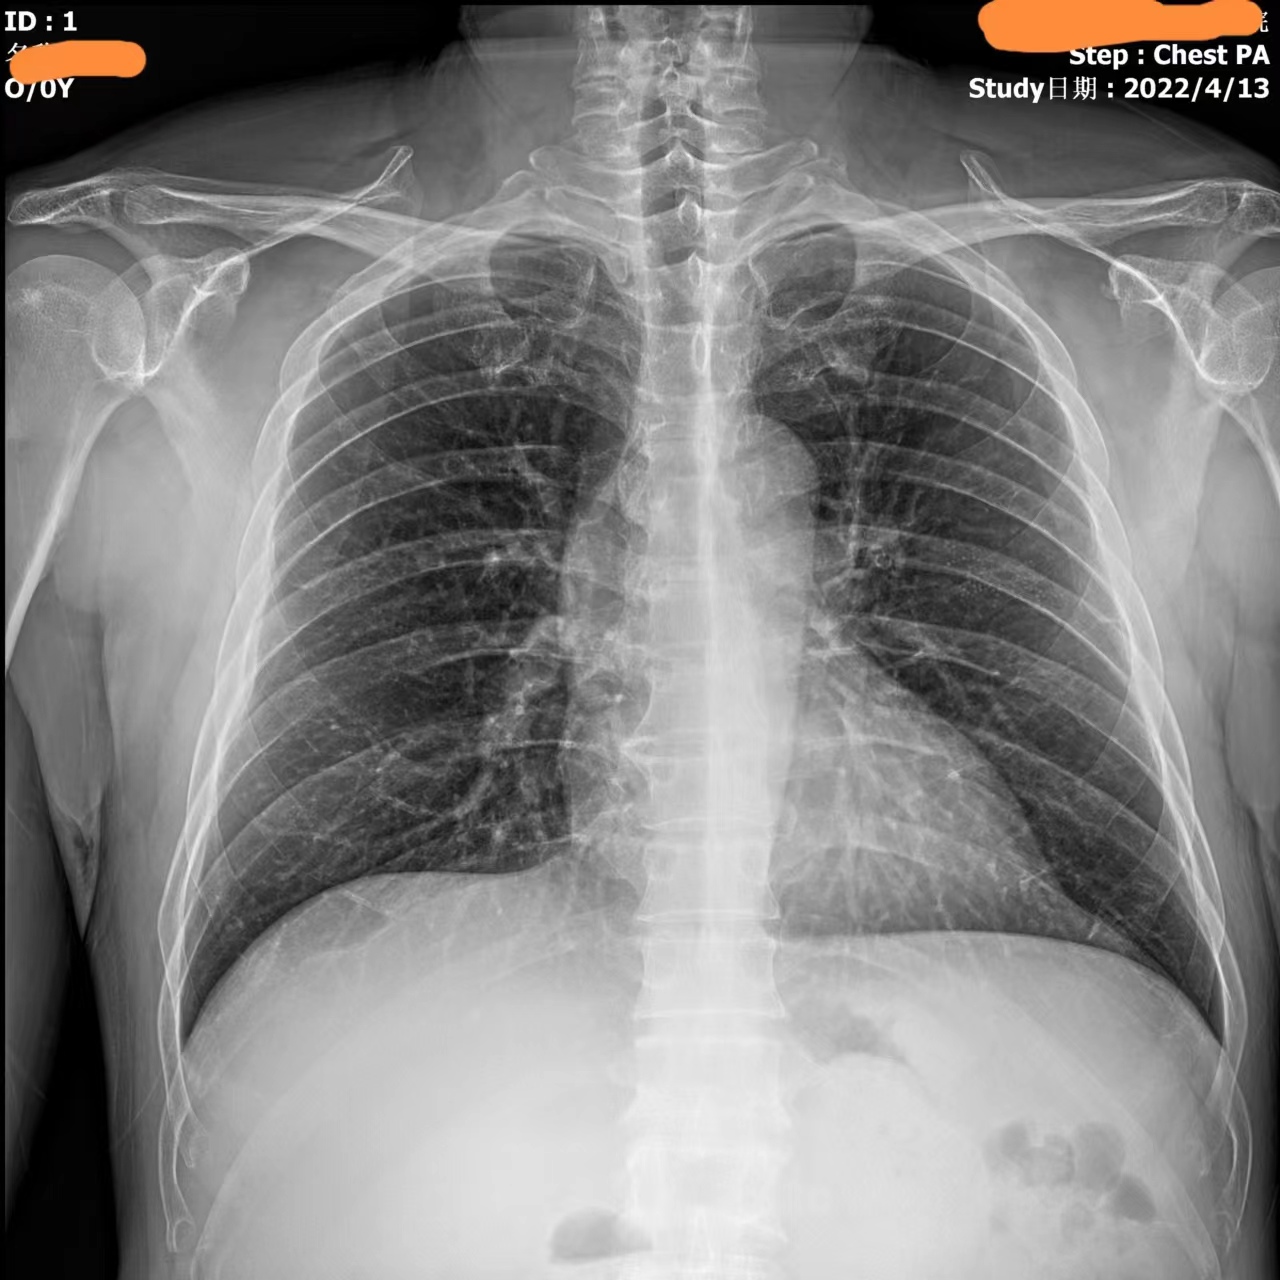

Видео с этого устройства выглядит следующим образом: